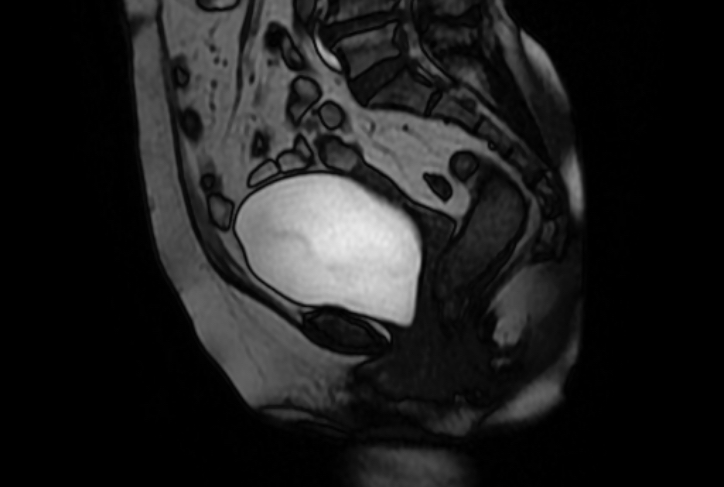

MRI diagnosis

Figure 8 MRI Sagittal image at rest

Figure 9 MRI Sagittal image on Valsalva

Pelvic floor ultrasound and MRI are the commonly used imaging modality in clinic. MRI has high resolution for soft tissue and high reference value for the selection of surgical methods. Yet it is expensive in examination cost and time consuming Ultrasonic examination is convenient and economical, and it is an effective method for screening and diagnosing pelvic floor dysfunction diseases.